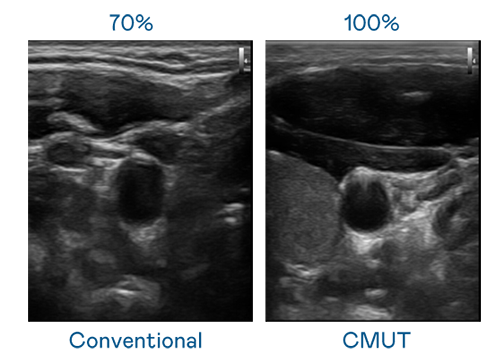

CMUT 技术是一种用电容式微机电元件来产生超音波讯号的技术。与传统 PZT 压电式技术相比,CMUT 频宽增加 30%,更宽频的超音波讯号让影像解析度大幅提升,是实现高影像品质医疗超音波扫描、促进精准医疗发展的关键技术。

超音波影像的解析度高低,首先取决于探头能发出的讯号频宽。AG庄闲 CMUT 可提供高清晰的超音波讯号,提供高频宽、高灵敏度、影像纹理细节更高的超音波影像,协助医护人员缩短影像判读时间及利用精准的医疗影像进行诊断。